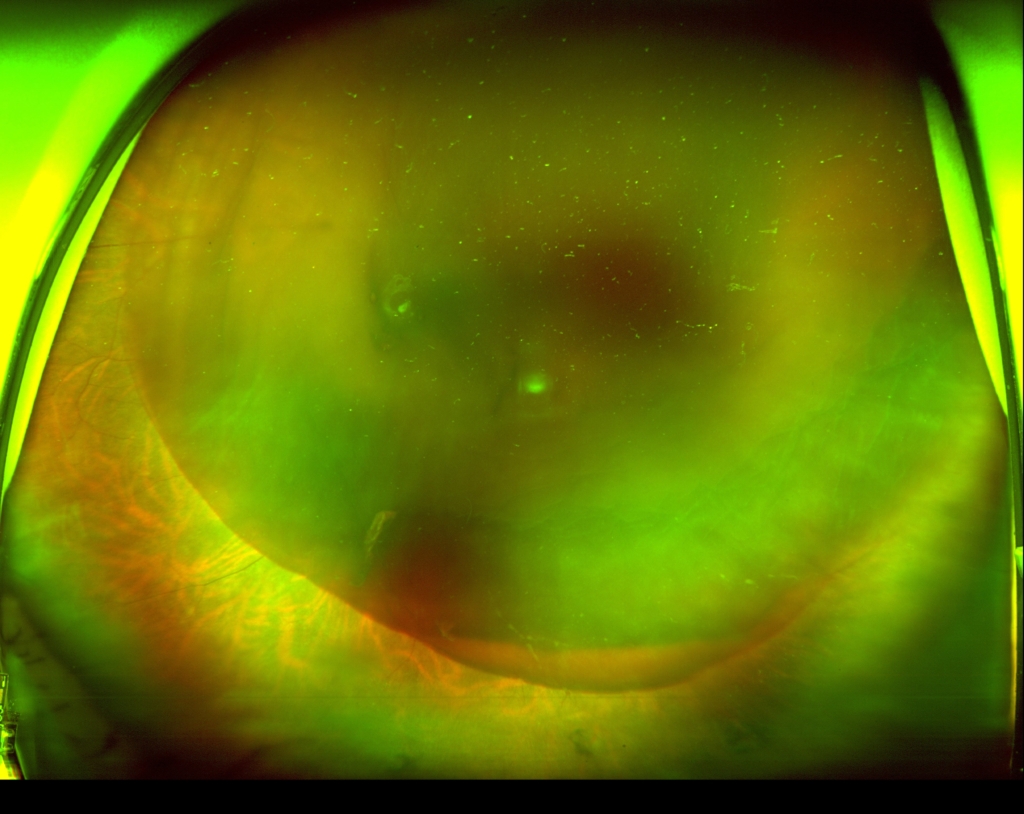

網膜前面に黄斑、乳頭を含む巨大な鏡面形成した硝子体膜下出血がみられる。

硝子体術中

術翌日 乳頭辺縁に軽度の出血見られるが、明らかな動脈瘤もなく出血の原因となる病変はなかった。